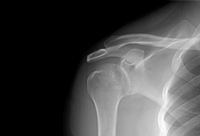

Joint dislocation

Anteroposterior x-ray view of a shoulder showing an anteroinferior dislocation